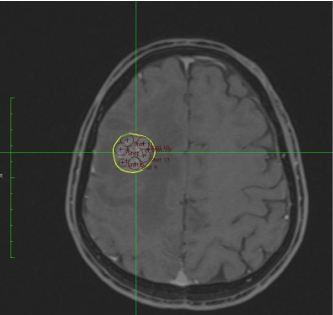

Hình 8. Hình ảnh lập kế hoạch xạ phẫu u não di căn trên phim MRI